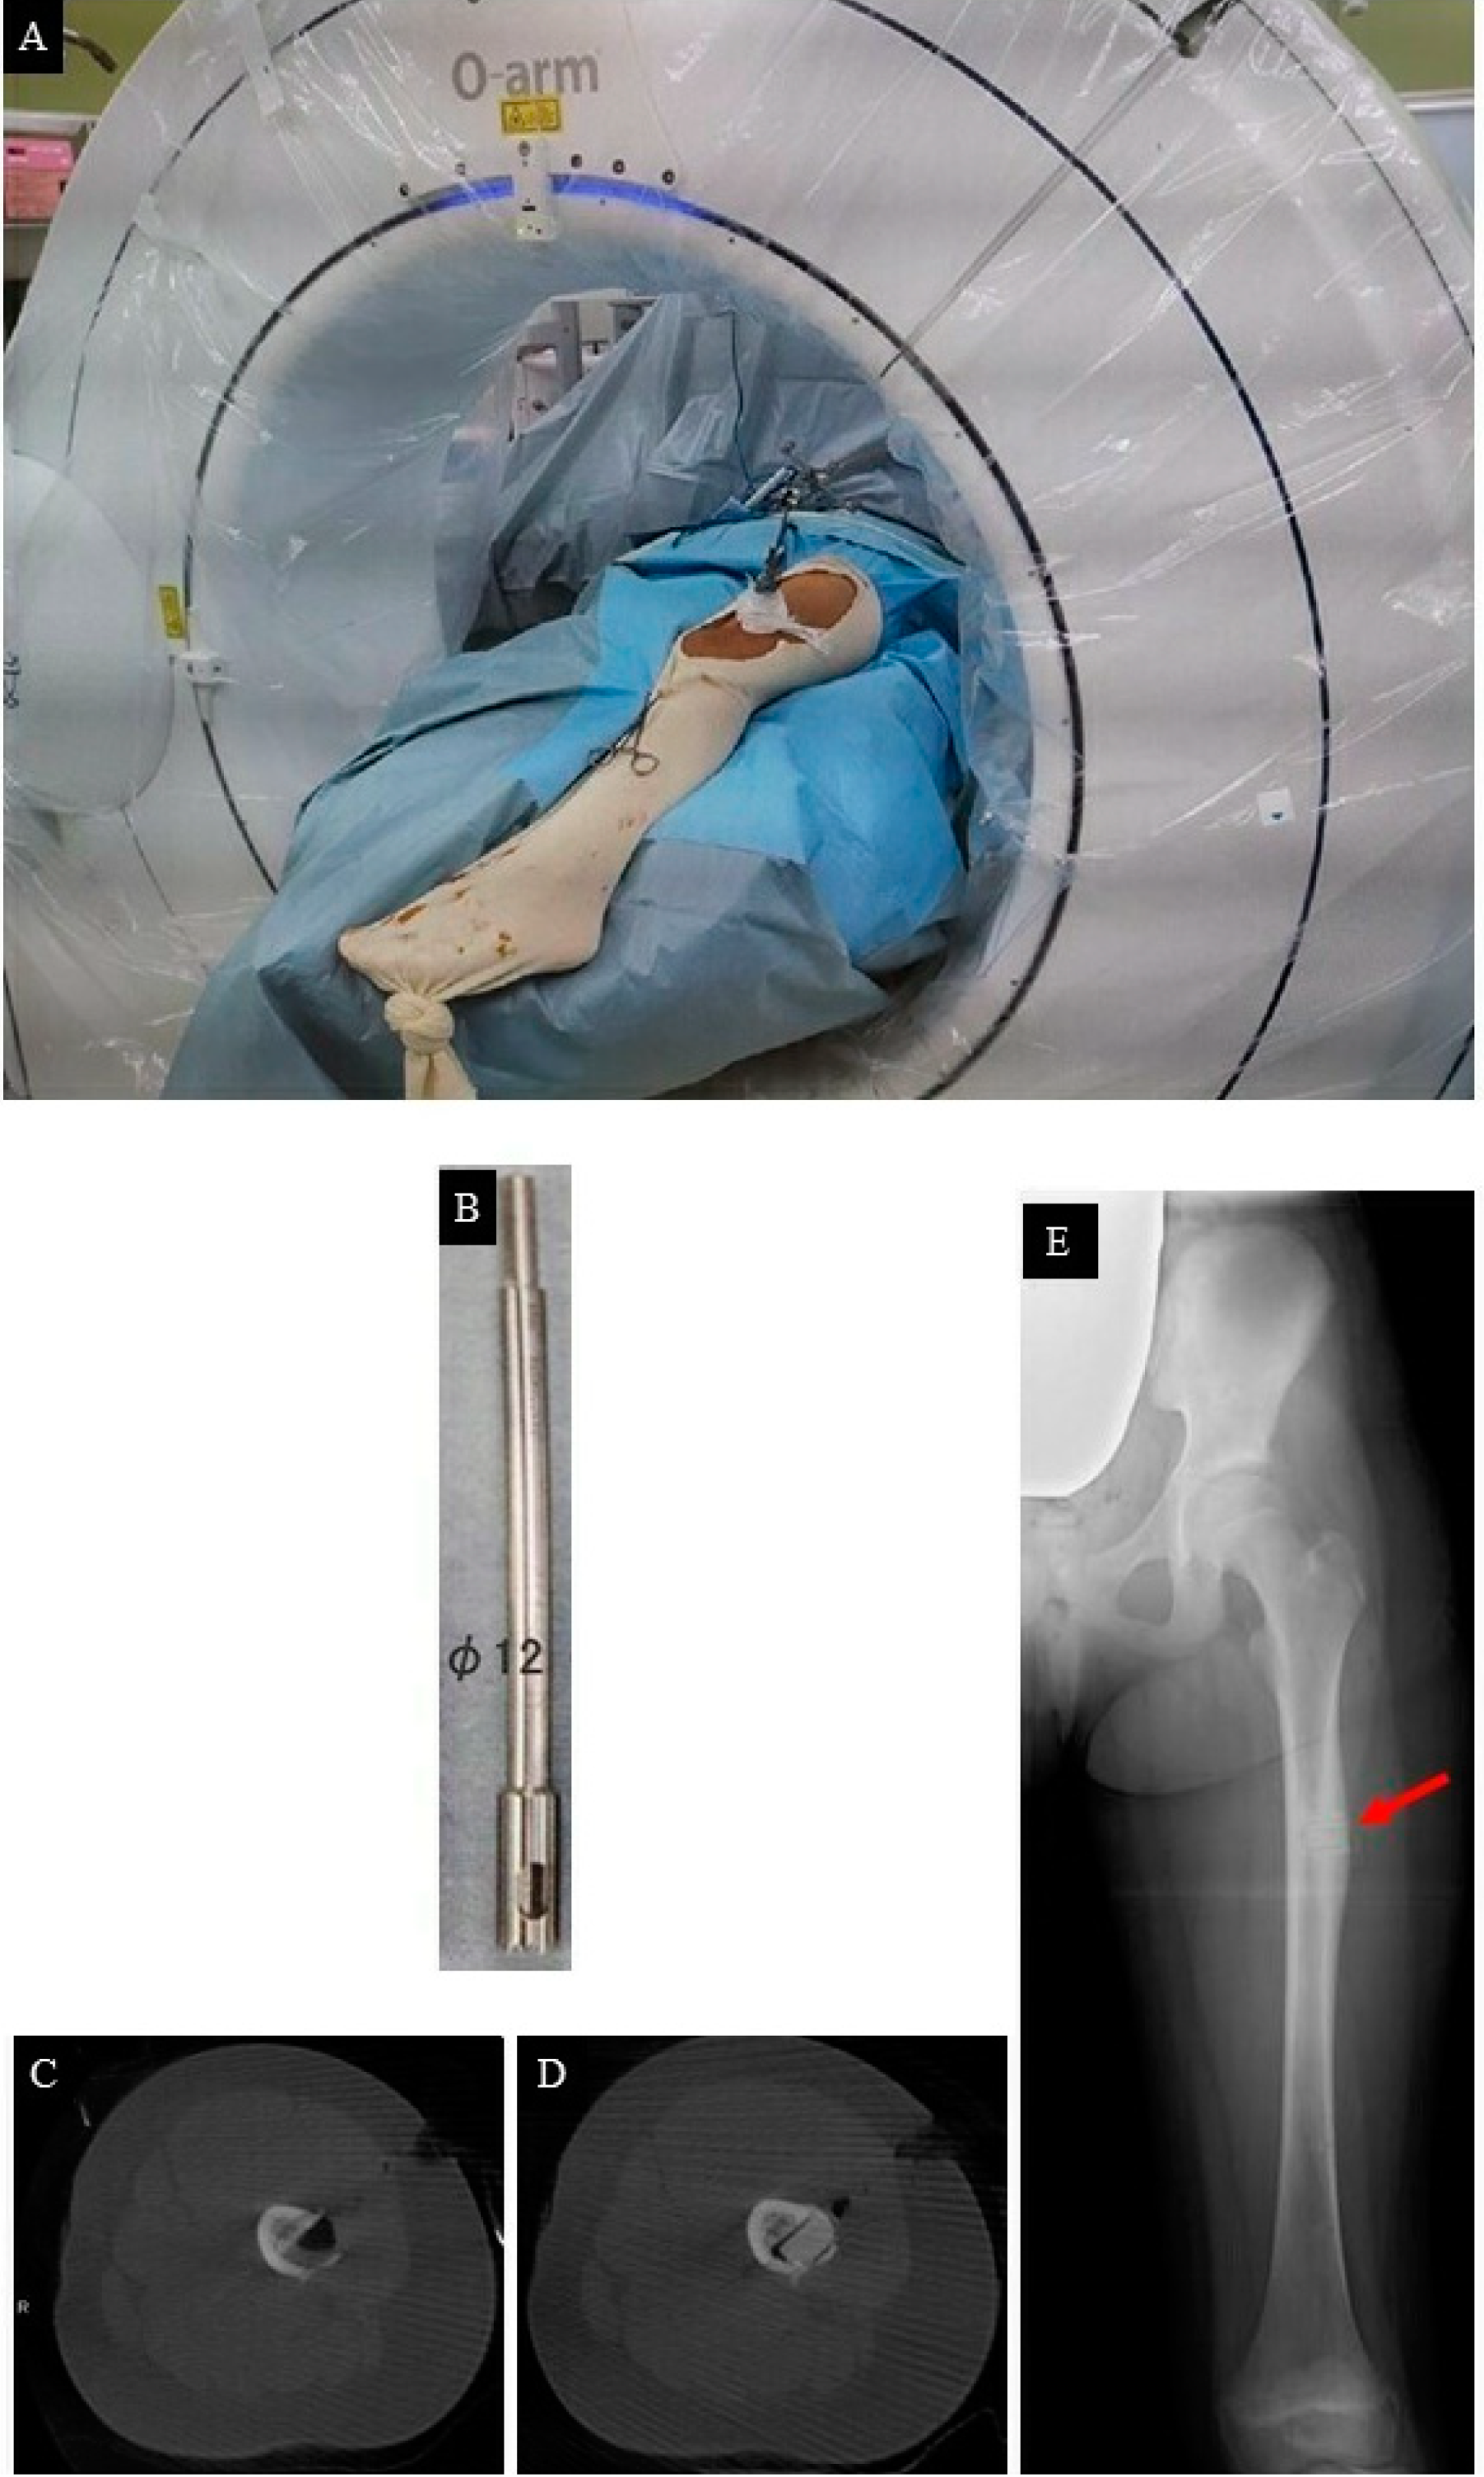

2. Case Presentation

- FEA to predict bone mechanical properties after the bone resection with the decided method, modified by tumor dimensions.

- Tumor resection and femoral stabilization, according to results of FEA.